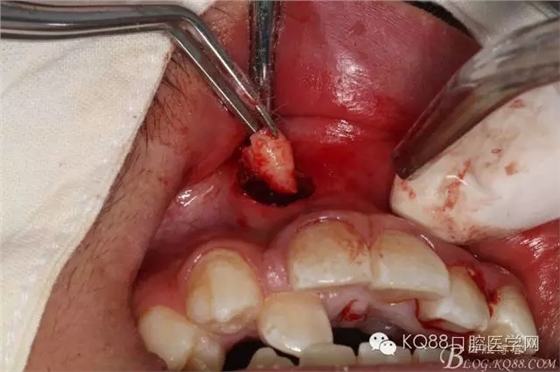

圖5.經過仔細認真的術前CBCT影像檢查分析,考慮手術進路及操作性,局部浸潤麻醉下,遂從唇側前庭溝處做弧形小切口、翻瓣。渦輪鉆去骨后的臨床情形:完美的弧形切口。去除唇側的骨板、顯露出部分多生牙的牙根和少量牙冠,位置之高,令人吃驚、一定要注意11的牙根,防止損傷11根尖。